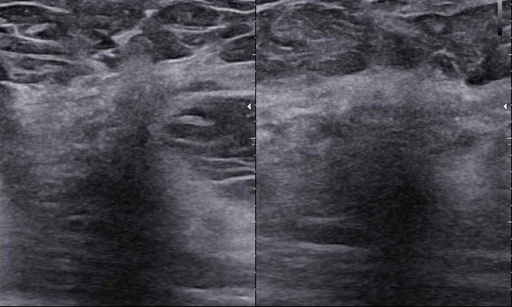

Webinar: BI-RADS-usg case story. Czy my rzeczywiście potrafimy czytać tę skalę? Dlaczego tyle jest rozbieżności?

Czy my rzeczywiście potrafimy czytać tę skalę? Dlaczego tyle jest rozbieżności?

Czy podział BIRADS 4 ma sens? Jak radzić sobie  z BIRADS 4a, b, c?